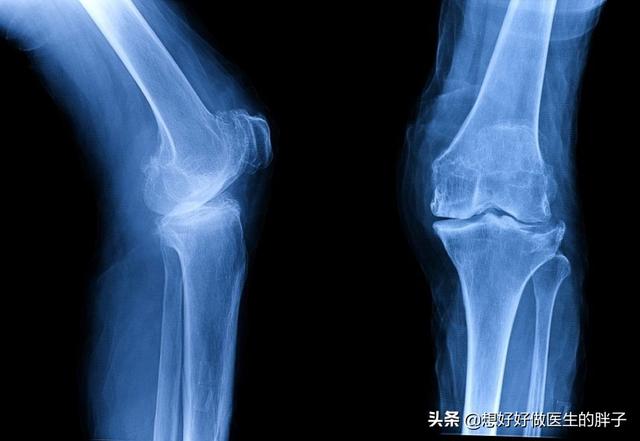

随着年龄的增长、对于关节的使用、体重的增加,关节内的软骨都有可能会发生磨损,而关节内的软骨一旦磨损以后就会导致骨关节炎,患者会出现关节屈伸的疼痛,有的患者严重的时候不敢下蹲,继发比较明显滑膜炎的时候会有关节的积液。随着病情的进展,患者关节会有大量的骨赘形成,严重的患者会出现明显的关节畸形,不能正常的蹲起,关节的活动也会因为骨髓的阻挡导致不能正常屈伸。

针对于这种情况,最好还是要明确关节腔内软骨磨损的具体情况,建议患者不仅要进行膝关节x线检查,还应该检查膝关节的核磁,如果关节内软骨磨损不是特别的严重,可以给予患者关节内注射玻璃酸钠或者是prp来增加软骨的弹性,尽量润滑关节,帮助患者减轻症状。随着症状的减轻,患者的行动力也会有所增加,如果在进行科学的康复锻炼,强化关节周边的肌肉,那么症状就会有所缓解。

而如果膝关节问题比较严重,关节活动已经出现了明显的受限,关节软骨磨损的特别严重,那么应该进行膝关节置换手术,帮助患者解决疼痛的问题以后再进行更加系统的康复锻炼,尽量帮助患者恢复到日常生活当中去,比如像下图这样的x线,表现患者关节腔内的软骨可能已经磨损消失殆尽了,这种情况如果患者疼痛比较严重,进行关节置换是最好的选择,否则患者膝关节疼痛、酸疼、无力的症状很难改善。